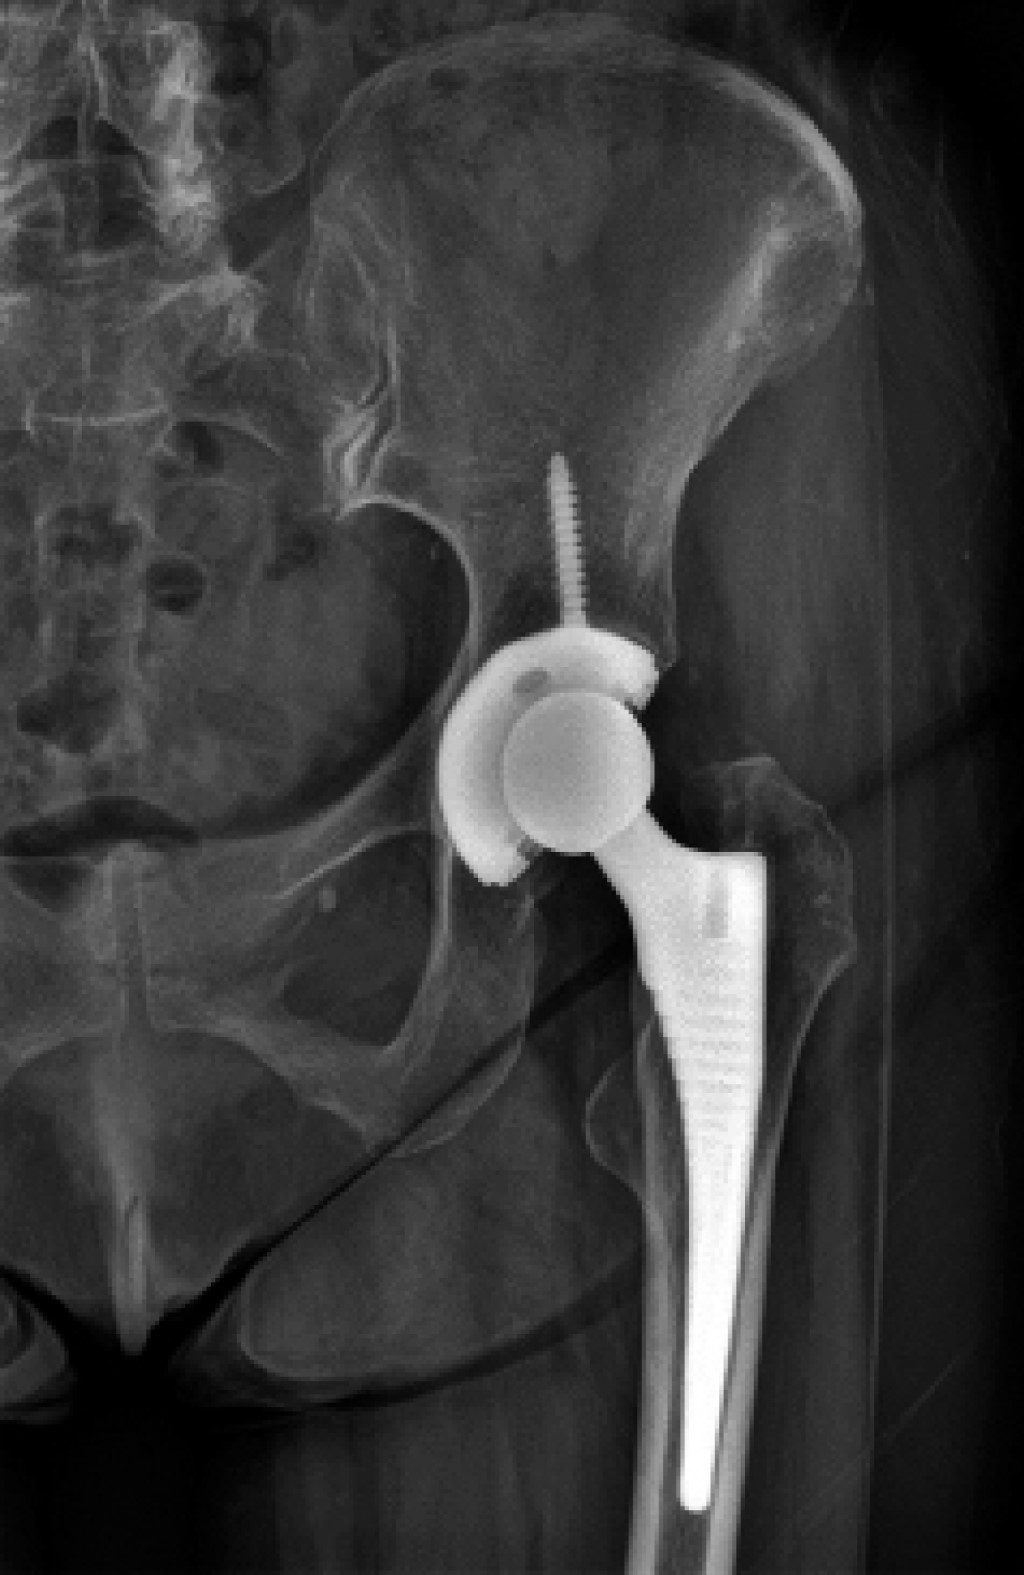

Como protocolo diagnóstico, se solicitó una radiografía anteroposterior de pelvis en la cual se observó el estado de los componentes protésicos sin cambios a comparación de la radiografía inicial posterior a la artroplastia total de cadera izquierda, con lo cual se descartó aflojamiento aséptico o fatiga del material (Figura 1). También una resonancia magnética no contrastada en la cual se observó tendinosis insercional del glúteo menor y avulsión > 50% anterior de la inserción del glúteo medio con infiltración grasa en menor cantidad a las fibras musculares de su vientre muscular (Figura 2).

Dentro de los estudios de gabinete que deben ser solicitados, se inicia con una radiografía anteroposterior de pelvis para descartar diagnósticos diferenciales, como alteración en la posición de los implantes y en el offset, así como datos de aflojamiento periprotésico.2 García y colaboradores describen el ultrasonido como un método fiable para detectar y medir la extensión de las rupturas de los tendones abductores; sin embargo, continúa siendo operador dependiente.3 La artrografía es un estudio poco específico para diagnosticar esta patología2 y la resonancia magnética es el estudio más sensible y específico para clasificar roturas de los tendones de los músculos abductores. En esta última, se pueden observar cambios de intensidad en las zonas de lesión y la presencia o no de degeneración grasa muscular. La única desventaja de la resonancia magnética es que puede llegar a sobreestimar el número de lesiones de aparato abductor cuando se correlaciona con la clínica.4

Figura 1